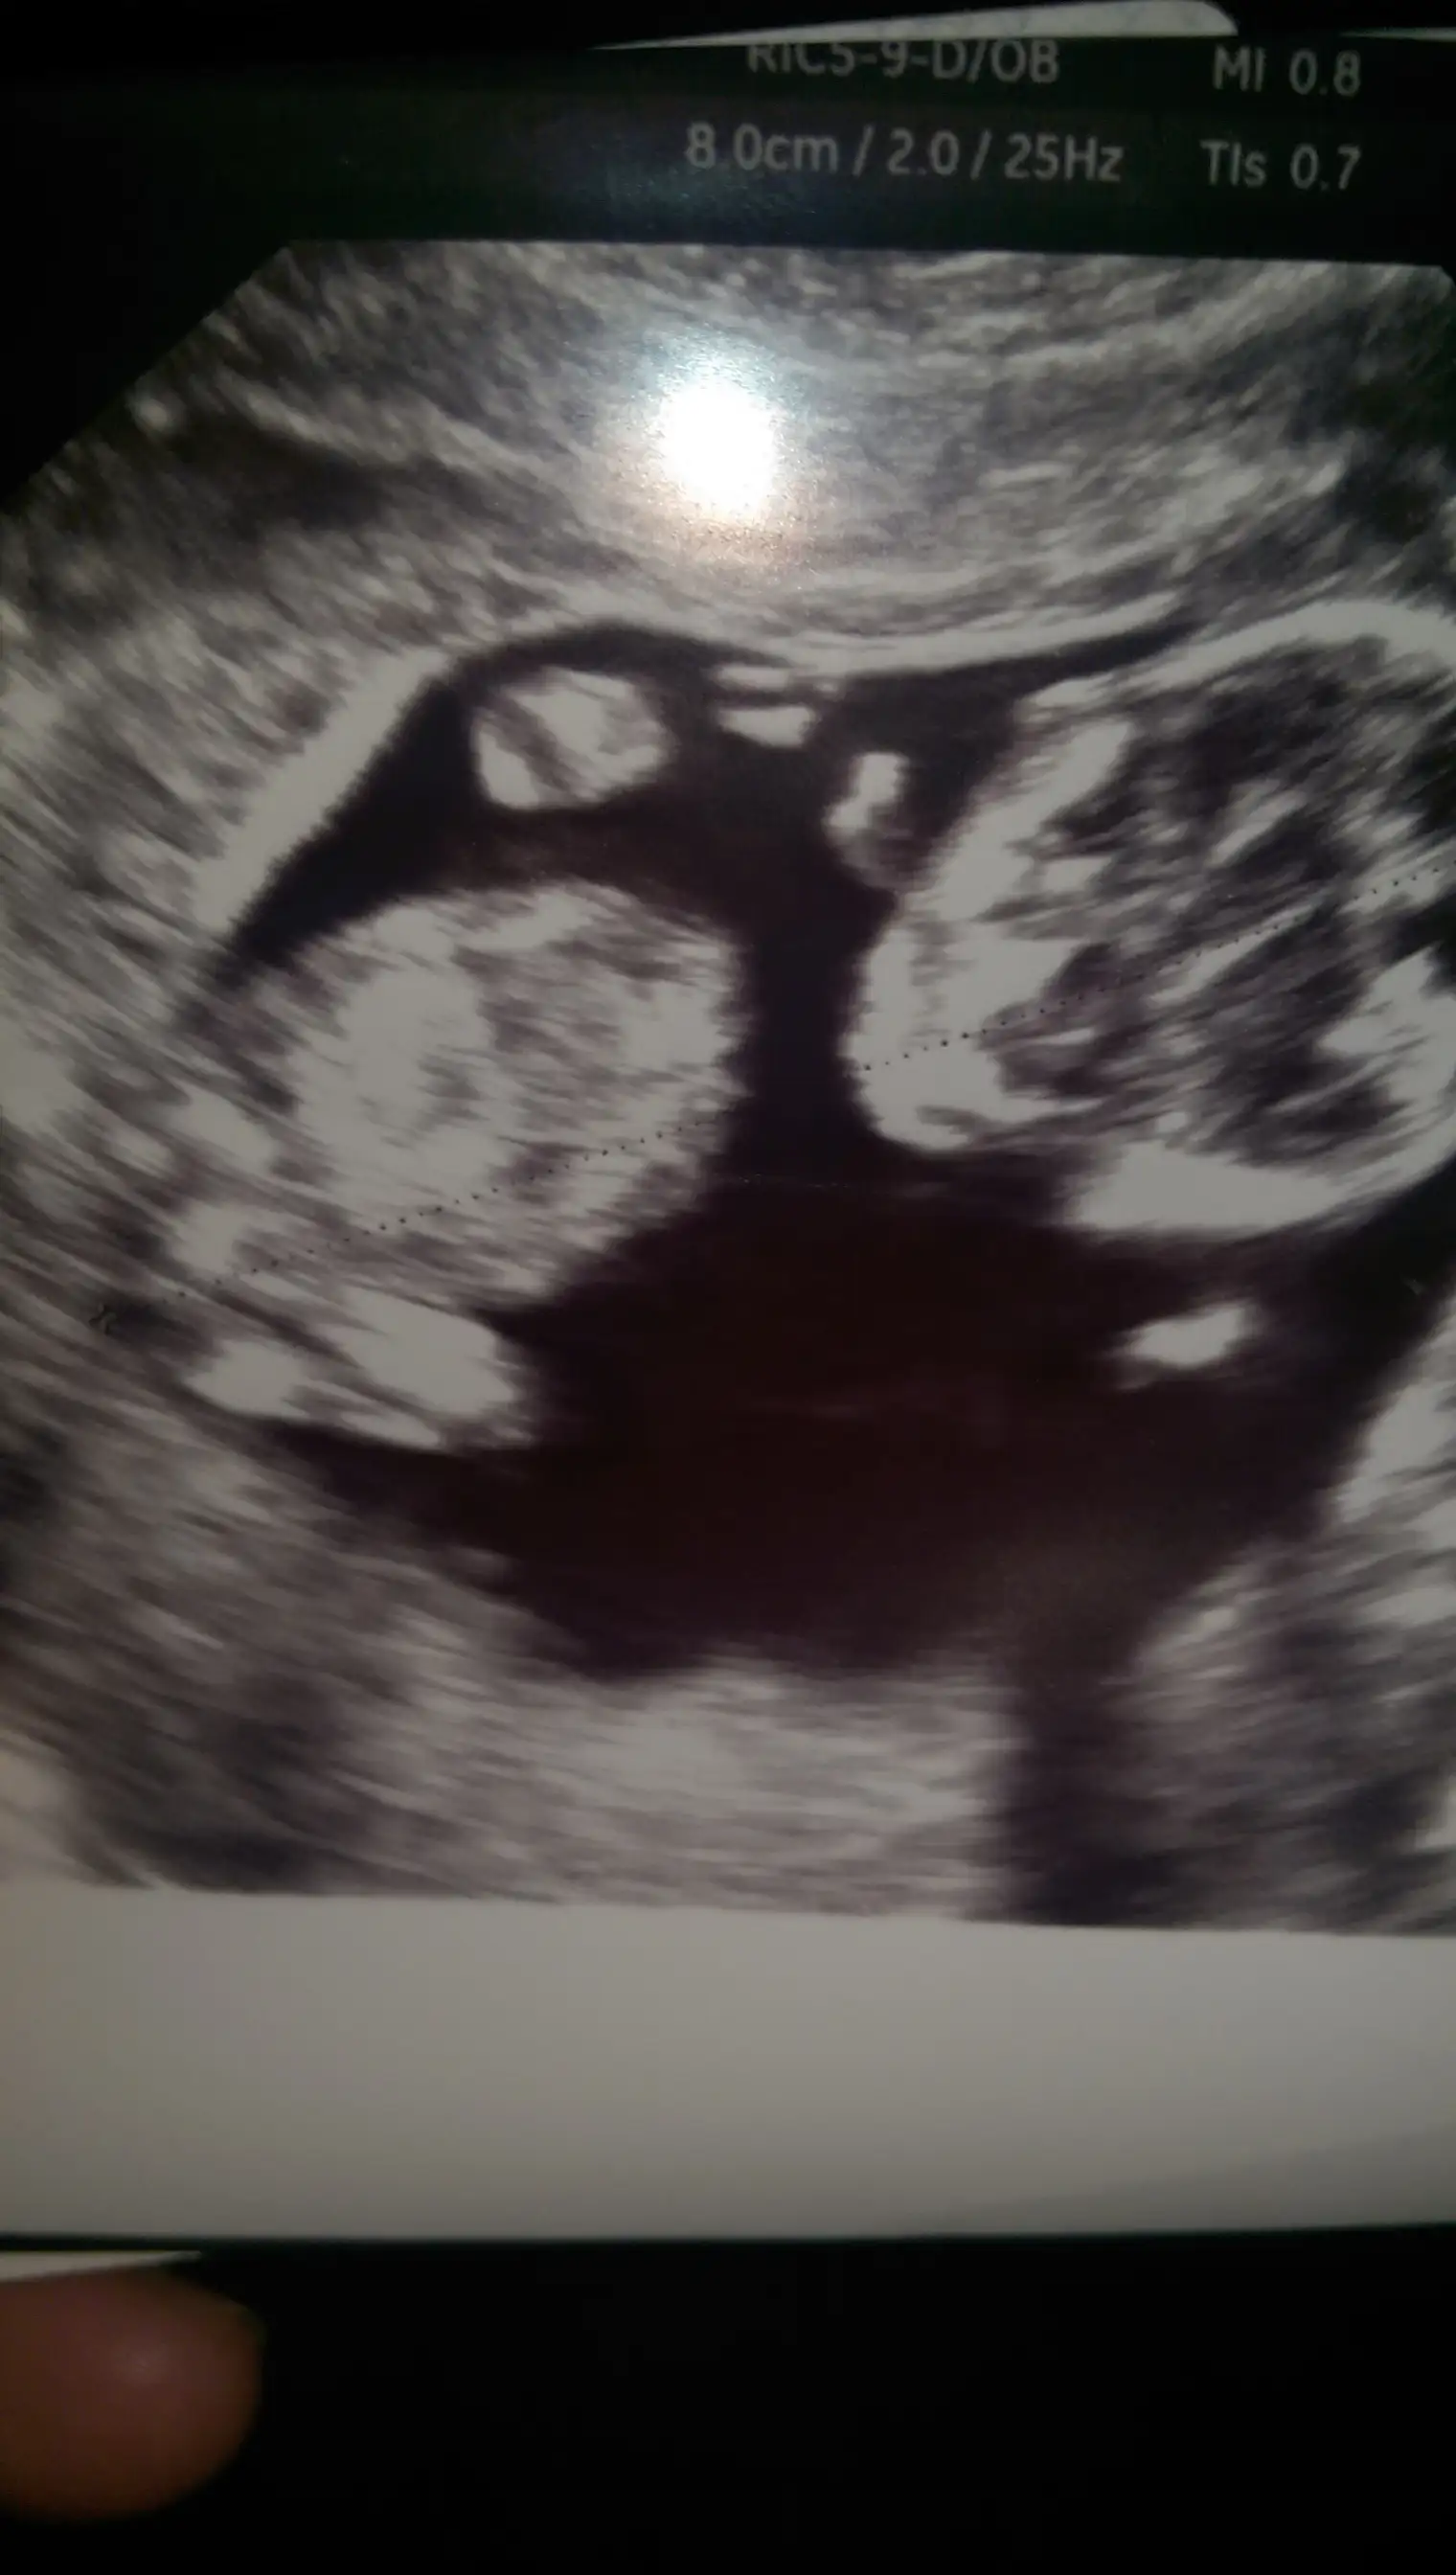

Ustteki fotoda erkek gibi eger kordon degilse digerlerinde kiz gibi doktor bisey dedimi

Eki Görüntüle 1311949